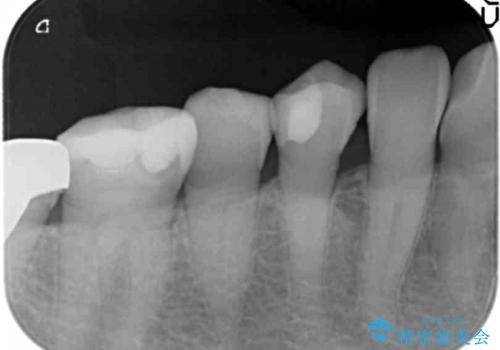

- 歯が欠けて舌が引っかかることを主訴に来院された患者様です。

精査したところ、右下小臼歯(右下4)が欠けていました。

古いレジンを取り除いてしっかり治療したいという患者様のご希望により、セラミックインレーによる修復を行いました。

自然な仕上がりと咬み心地に喜んで頂けました。

インレーの種類:e-max press セラミックインレー